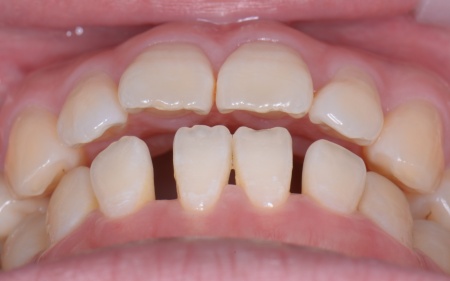

| カウンセリング | 拝見したところ、右上と左下の奥歯に強い痛みが出ていました。 レントゲンで確認した結果、どちらも歯の根が割れていることが判明しました。 歯の根が割れたまま放置すると噛むときの痛みが続くだけでなく、炎症が広がって周囲の歯や骨にまで影響を及ぼすおそれがあります。 また、上下の歯を噛み合わせた際に前歯が噛み合わず隙間ができる開咬(かいこう)と呼ばれる噛み合わせも見られました。 以上のことから、抜歯後に歯を補う治療と噛み合わせを改善するための治療が必要と診断しました。 |

患者様は「健康な歯をできるだけ守りたい」との理由から、③のインプラント治療を希望されました。 まず、右上と左下の奥歯を抜歯しました。 矯正がある程度進んだ段階で、右上と左下のインプラント手術を実施しました。 インプラント手術後は矯正治療の仕上げを行い、装置を外しています。 治療終了後、下前歯の間に見られる三角形のすき間(ブラックトライアングル)が気になるとのご相談がありました。 |